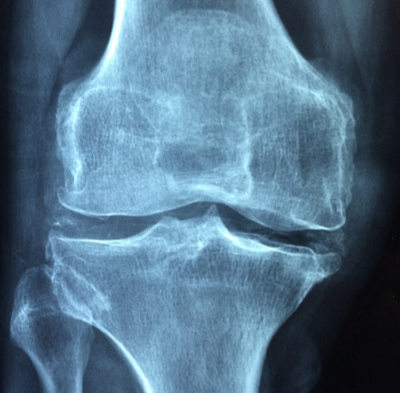

관절염에는 크게 퇴행성 관절염과 류마티스 관절염이 있다고 합니다. 두 질환을 구분하는 가장 큰 포인트는 염증의 출발점입니다. 퇴행성 관절염은 우리가 잘 알고 있는 연골에서 염증이 시작되고, 류마티스 관절염은 연골 보다 외측에 있는 활막이라는 곳에서 염증이 시작된다고 합니다.

2013년 퇴행성 관절염과 관련된 연구에 의하면, 특정 관절 염증은 관절에 기계적으로 유발된 손상으로 인해 발생한다고 합니다. 연구에서는 '신체 역학'이라는 용어를 사용하는데, 여기서 신체 역학이라는 것은 신체가 움직이는 방식을 말한다고 하며, 관절·근육·신경이 포함된다고 합니다.

신체 역학이 나쁘면 관절·근육·신경이 정상적이지 않게되어 바르지 않은 움직임을 하게 되고, 이러한 움직임이 관절에 자극을 주어 관절을 나빠지게 만들어 결국 통증을 유발한다고 합니다. 잘못된 신체 역학을 개선하지 않고 방치하게 되면 만성 통증과 염증 및 부상으로 이어질 수 있다고 합니다. 한편, 관절이나 관절 주위의 부상은 관절 염증을 더욱 악화시킬 수 있는데 여기서 부상이 장기화되면 근육의 약화 및 신체 역학 저하로 이어져 관절 염증을 더욱 악화시킬 수 있다고 합니다.